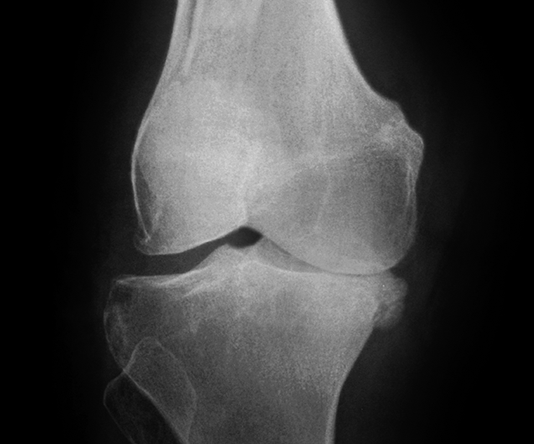

Thoái hóa khớp gối giai đoạn 1

Ở giai đoạn đầu tiên, khớp gối chưa có dấu hiệu bất thường cho thấy bị thoái hóa khớp gối. Bệnh nhân đi lại bình thường, chưa xuất hiện cơn đau khớp hoặc có thể chỉ đau khớp gối khi đứng lên ngồi xuống, ngồi xổm, lên xuống cầu thang. Khớp gối cũng chưa bị sưng và không biến dạng. Nếu chụp thêm MRI có thể thấy khớp gối gần như bình thường.